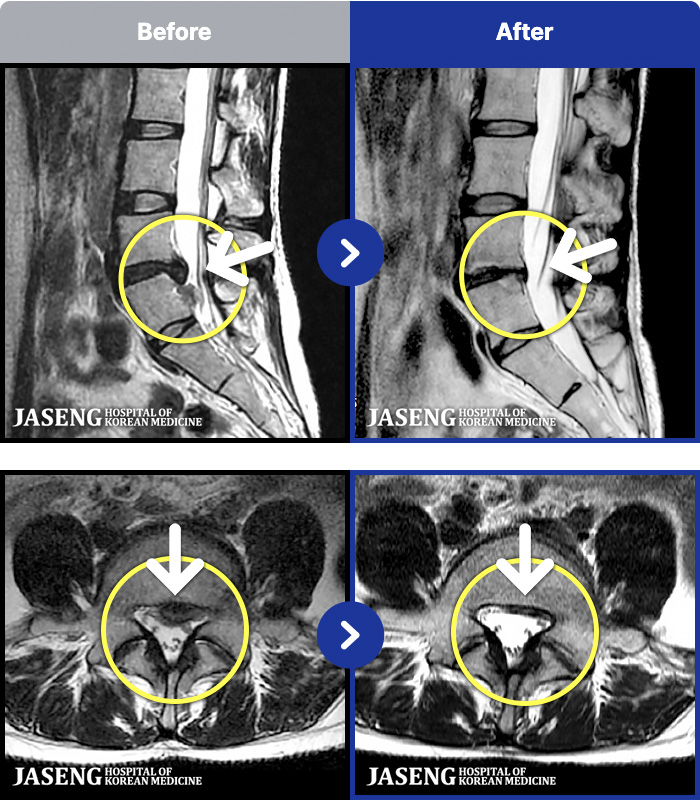

ȯںп Ǹ ǿ ԿǾ, ο ġ ۿ Ƿ ġḦ Ͻñ ٶϴ.